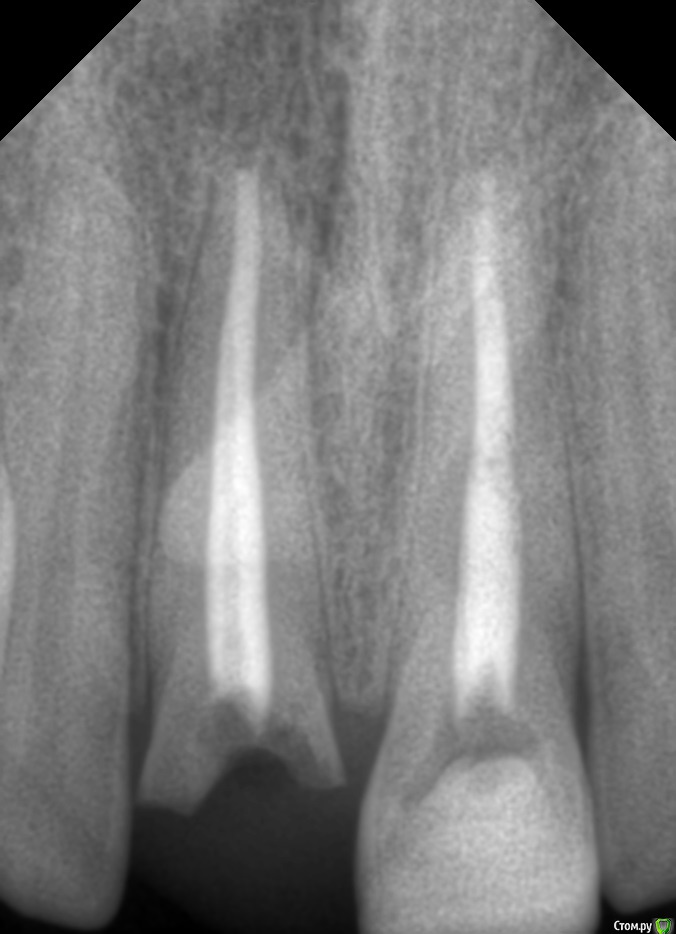

Andrey52 Опубликовано 25 декабря, 2015 Автор Поделиться Опубликовано 25 декабря, 2015 вероятность кисты на 1.1 Вас не смущает? Или ее нет меня просто обманывают?? Ссылка на комментарий

red_butler Опубликовано 25 декабря, 2015 Поделиться Опубликовано 25 декабря, 2015 вероятность кисты на 1.1 Вас не смущает? Или ее нет меня просто обманывают??по этому снимку судить нельзя, для уточнения сделайте Кт 1 Ссылка на комментарий

IvanK Опубликовано 25 декабря, 2015 Поделиться Опубликовано 25 декабря, 2015 вероятность кисты на 1.1 Вас не смущает?сомнительно 1 Ссылка на комментарий